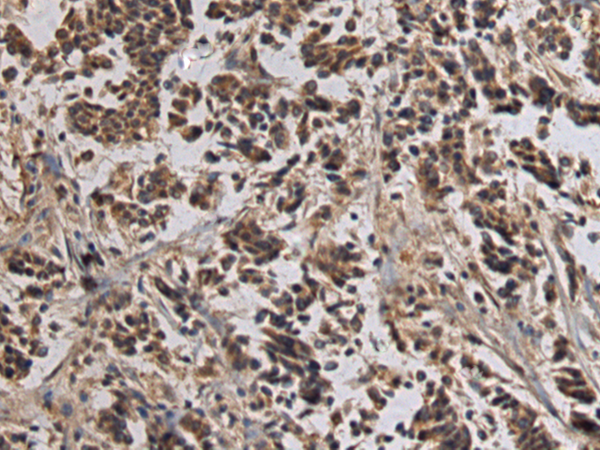

IHC positive control:

Human breast cancer

IHC Recommend dilution:

100-300